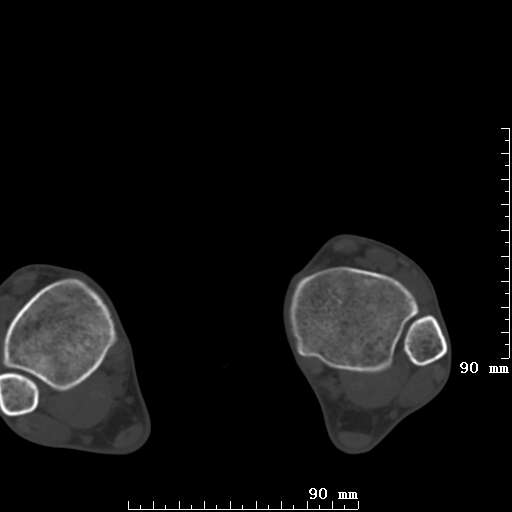

标题: CT19820:外伤一天,如何定性.男27Y [打印本页]

标题: CT19820:外伤一天,如何定性.男27Y

排除下创伤性关节炎吧,距骨有些囊变和硬化,周围韧带软组织有些机化、钙化。不是很像距骨无菌性坏死,感觉在关节面上的多,而不是距骨里面。

未见骨折及脱位像。距骨像是剥脱性软骨炎

支持!(踝关节距骨表面囊变和硬化 缺损)

距骨剥脱性软骨炎可能;踝关节创伤性关节炎?

未见明确新鲜骨折改变,距骨剥脱性软骨炎或踝关节创伤性关节炎可能。

距骨像是剥脱性软骨炎

关节周围多发高密度影,要结合病史

距骨像是剥脱性软骨炎。